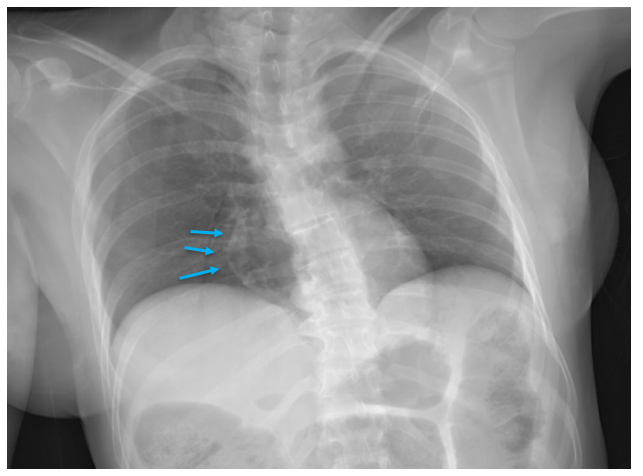

The second pathway by which we reach an undetermined manner is when extensive decomposition or other soft tissue loss (such as fire damage) interferes with our ability to determine a cause of death. Think of completely skeletal remains discovered in an abandoned building. Sometimes, indicators of potentially lethal injuries can still be identified – for example, a gunshot wound of the skull or knife marks on a rib. But, as the aphorism goes, “an absence of evidence isn’t necessarily evidence of absence” – a bullet or blade could be lethal while only striking soft tissue (especially in regions like the abdomen or neck). If we cannot rule out non-natural causes of death, the best choice for manner is “undetermined.”